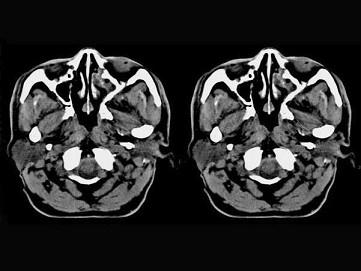

问题 男,61岁,流鼻血三天。如图所示最可能的诊断为 ( )

选项 A、小唾液腺瘤 B、鼻咽部息肉 C、鼻咽腺样体增生 D、鼻咽纤维血管瘤 E、鼻咽淋巴滤泡增生

答案 E